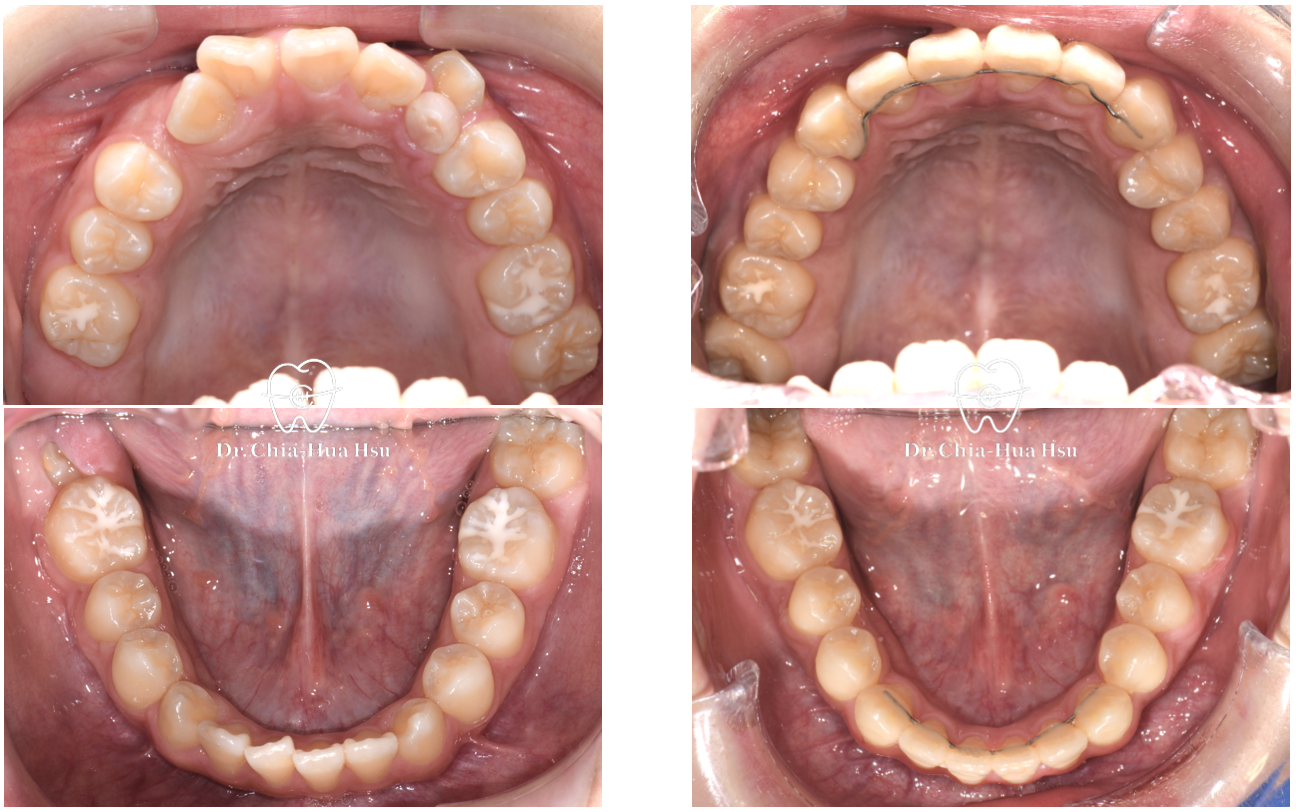

上顎擴弓前

上顎擴弓後

使用上顎擴弓器將上顎牙弓撐寬,一天兩轉(早晚各一次),每轉一次大概可以撐寬 0.25 cm。

大概二至四週後,門牙之間會有明顯縫隙出現,代表上顎骨縫有成功撐開!上顎撐寬後,就可以把擁擠的牙齒排進牙弓中囉!